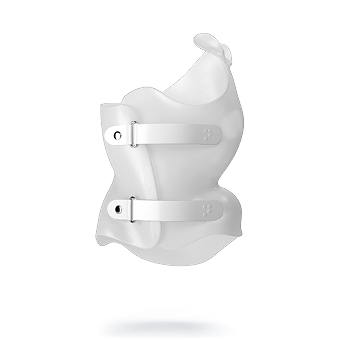

هل كل الأطفال يحتاجون نفس نوع الحزام؟

لا، يتم تصميم الحزام حسب حالة كل طفل.

التطور الكبير في تصميم الأحزمة الطبية جعل علاج اعوجاج العمود الفقري عند المراهقين أكثر نجاحًا وأقل إزعاجًا. باستخدام تقنيات التصوير الثلاثي الأبعاد والمحاكاة الرقمية، أصبح الحزام أكثر خفة وراحة، ويعطي نتائج أفضل في تصحيح الانحناء والتواء العمود الفقري.

امنح طفلك فرصة أفضل لمستقبل صحي مع حزام PioBrace المتطور من مركز الرواد. يتميز هذا الحزام بتقنيات تقويم متقدمة تضمن نسبة تصحيح عالية لاعوجاج العمود الفقري، مع اعتماد فريق طبي متخصص يراقب التقدم بشكل مستمر لضمان عدم تفاقم الانحناء مستقبلاً. اختروا مركز الرواد، حيث تلتقي الخبرة الطبية بأحدث الابتكارات، لنوفر لطفلكم علاجًا مخصصًا وآمنًا يعيد التوازن لجسمه بثقة واحترافية. صحتهم أمانة ونحن هنا لنحافظ عليها.

لماذا يجب عليكم اختيار حزام PioBrace؟

- راحة استثنائية: يتميز حزام PioBrace بتصميمه الذي يوفر أقصى درجات الراحة للأطفال طوال فترة العلاج.

- فعالية مثبتة علميًا: يساعد الحزام في إيقاف تقدم الاعوجاج وتقليل الحاجة إلى التدخل الجراحي.

- سهولة الاستخدام: يمكن ارتداؤه لفترات طويلة دون التسبب في أي إزعاج للأطفال.

- موثوقية وجودة عالية: يُصنع بأحدث التقنيات لضمان أقصى درجات الراحة والكفاءة.